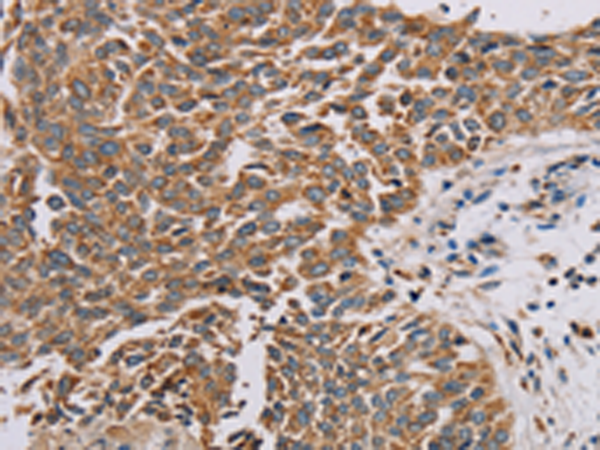

分类: 科研抗体货号: P08529别名: ZRF; MTF-1应用: IHC反应种属: Human